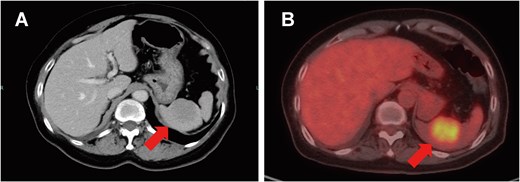

On clinical examination, a 4-cm ill-defined mass was palpated in the right breast, accompanied by a positive dimpling sign. Mammography showed an ill-defined, high-density mass in the upper-outer quadrant. Ultrasound revealed a 34-mm hypoechoic lesion with irregular margins and two swollen subclavian lymph nodes without an echogenic hilum. Dedicated breast MRI showed a 45-mm irregular, enhancing mass with early wash-in/fast wash-out kinetics (BI-RADS category 4C). Contrast-enhanced CT and positron emission tomography-CT identified a right breast mass, enlarged subclavian lymph nodes, and a solitary 2-cm splenic lesion (SUVmax 5.5) without additional distant lesions (Fig. 1A and B).

Splenic metastasis. Contrast-enhanced CT (A) and positron emission tomography-CT (B) demonstrate a solitary 2-cm splenic mass (arrows).